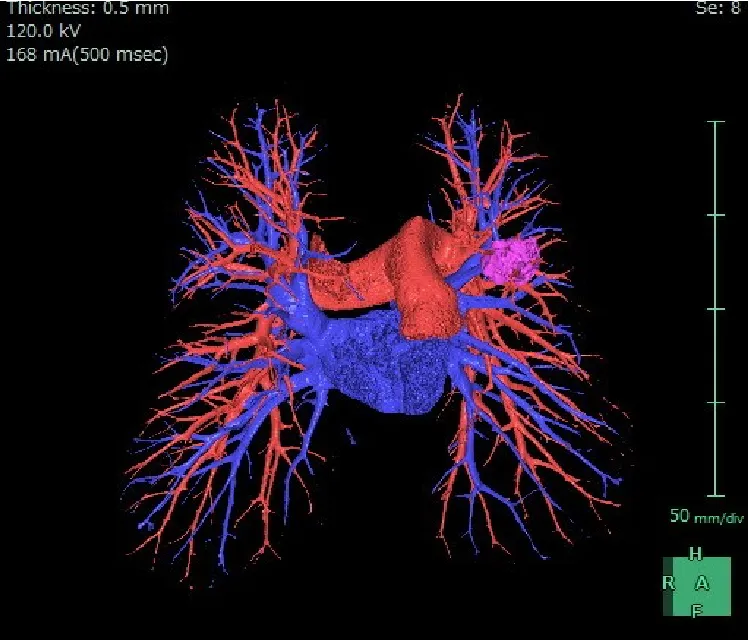

CTは Computed Tomography(コンピュータ断層撮影) の略で、X線を使って体の断面を撮影する装置です。体の内部構造を詳しく画像化できるため、さまざまな病気の発見に役立ちます。近年の技術進歩により、0.5mm間隔で断層画像を撮影できるため、ごく小さな病変も見つけることが可能になりました。また、得られた断面画像を重ね合わせることで、立体的な3D画像を作成することもできます。さらに、必要に応じて 造影剤 を使用すると、腫瘍などの病変部位がより明瞭に写り、周囲の血管の走行や栄養血管の状態を詳しく把握することができます。ただし、造影剤には副作用の可能性があり、また腎機能が著しく低下している場合には使用できないことがあります。造影剤を使うかどうかは、検査内容に応じて医師が判断します。